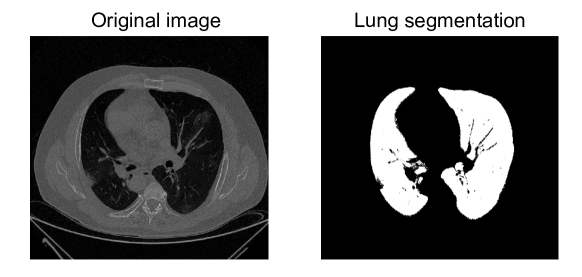

When working with medical images, it is crucial to apply preprocessing in order to improve the subsequent classification performance. Therefore, this operation must adapt images to the requirements of the classification framework. Given the high computational and memory requirements of CCT volumes, we downsampled the input images to obtain a final map of 128x128x128. We also performed an automatic lung segmentation in order to separate voxels corresponding to lung tissues from those of the surrounding anatomy. To do so, we employed features derived from the intensities and the histogram of the image, in addition to the Otsu’s method (Otsu, 1979) for computing the threshold that separated target and non-target voxels. This alternative relies on the maximization of the between-class variance to separate the voxels belonging to the different classes. Figure 2 shows the results obtained by the segmentation scheme.

Refer to caption

Fig. 2: Original image (left) and the one obtained after lung segmentation (right).